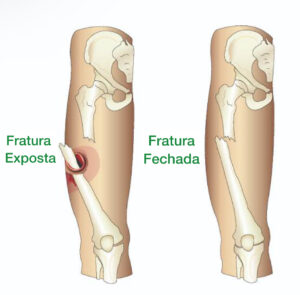

Ortopedia e Traumatologia Fratura Exposta: Entendendo as Fraturas Expostas de Fêmur e Tíbia Leia mais » novembro 15, 2024